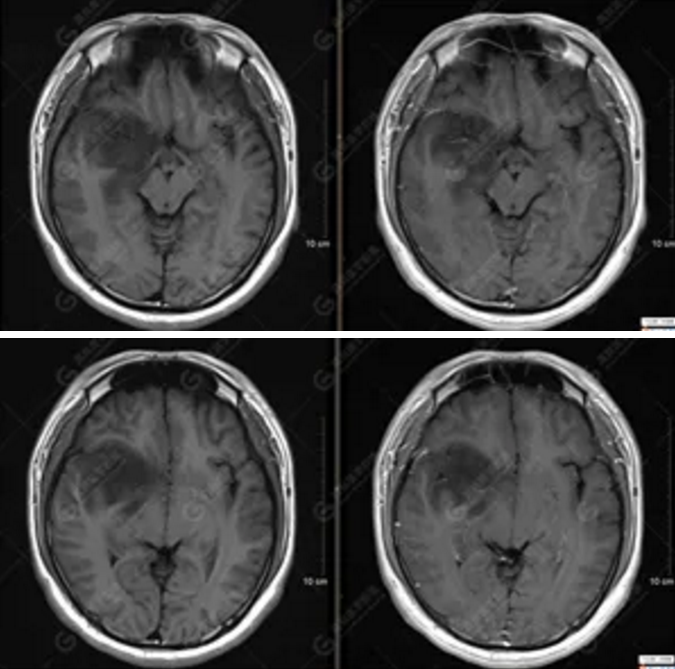

【MRI平掃及增強檢查所見】右側(cè)額顳島葉、右側(cè)海馬及右側(cè)基底節(jié)區(qū)見一團(tuán)塊狀異常信號影,累及右側(cè)下丘腦及視交叉,大小約5.1cm×4.5cm×4.3cm,呈長T1長T2信號,F(xiàn)LAIR序列呈等、稍高信號,DWI序列呈稍高信號,ADC圖高信號,增強后無明顯強化;病灶周圍見片狀長T1長T2水腫信號影,F(xiàn)LAIR序列呈高信號,病灶內(nèi)見右側(cè)大腦中動脈穿行。余腦實質(zhì)內(nèi)未見局灶性信號異常,增強后未見異常強化。右側(cè)側(cè)腦室輕度受壓,余腦室、腦池大小、形態(tài)均正常,中線結(jié)構(gòu)居中